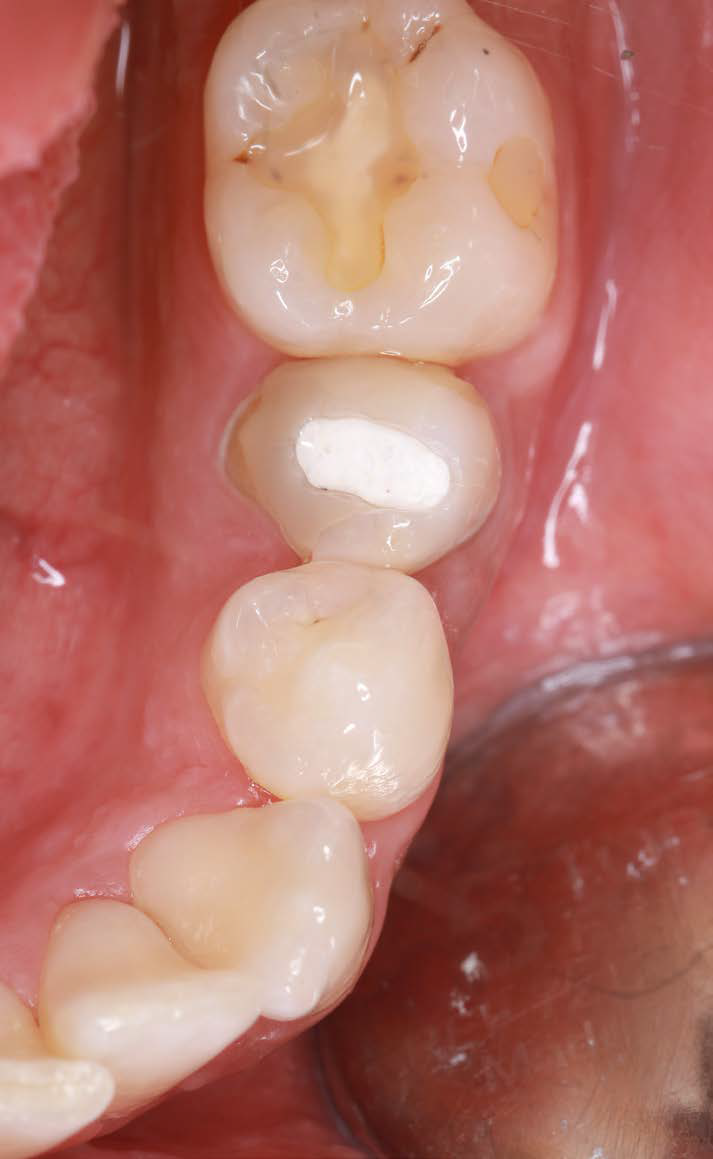

Figures 7 and 8: Clinical situation after 6 months

Figure 9: Clinical image after prosthetic restoration |

After six months, the soft tissue remained stable, and the papillae were well-formed. The case met all expectations for “pink-white aesthetics.” I was very satisfied with both the surgical and prosthetic results.